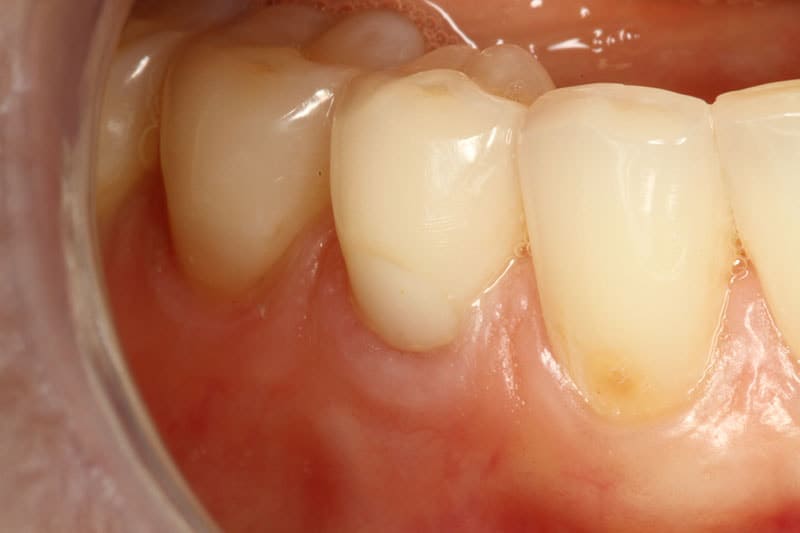

After treatment After